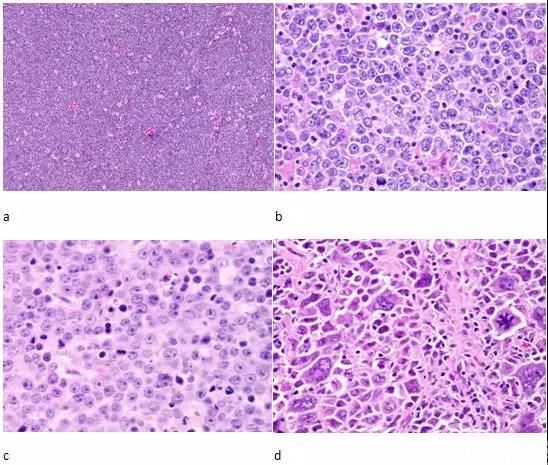

图文解析弥漫大B细胞淋巴瘤(DLBCL) – 91360智慧病理网

图说 非霍奇金淋巴瘤(下篇)_蕈样肉芽肿_皮肤淋巴瘤样丘疹病_Burkitt淋巴瘤_医脉通